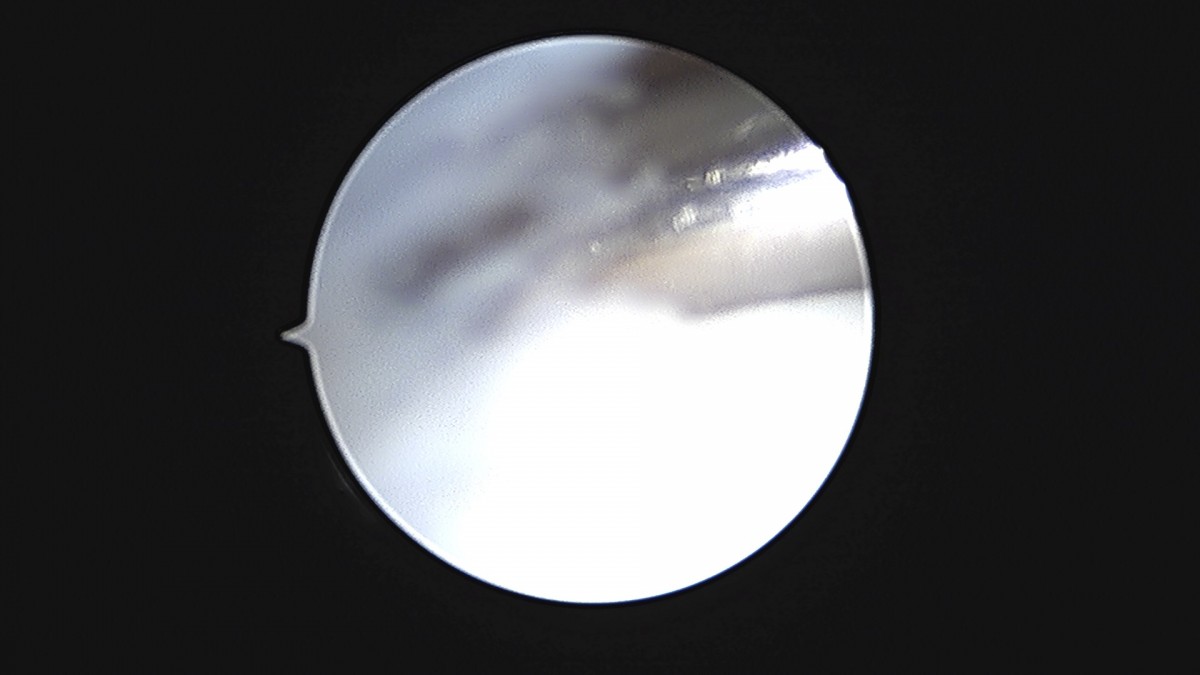

이재상원장님 발목 연골병변 제거술 및 골수 자극술 장경O 환자

dae765e4d9ac96aee867c9d6292d8784_1758006813_0984.jpg